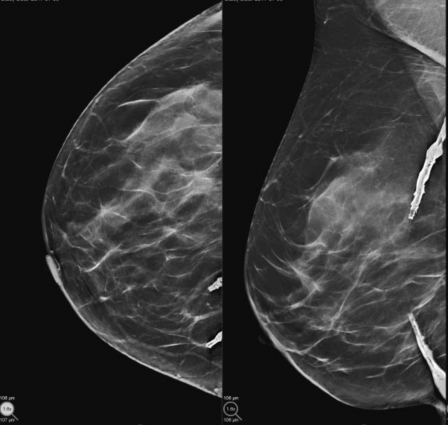

Se comunica un caso de una paciente de sexo femenino de 59 años de edad que fue sometida a la realización del estudio mamográfico de cribado anual, con las incidencias habituales cráneo-caudal y oblicuo-medio-lateral bilaterales. Se trató de una mama con áreas dispersas de densidad fibroglandular, en la cual se observaron calcificaciones gruesas de disposición lineal en la mama derecha proyectadas en el plano glandular profundo de los cuadrantes internos, con una solución de continuidad en el sector medio (►Fig. 1). Se recogieron los antecedentes clínico-ginecológicos de la misma, quien refirió la presencia de una válvula de derivación ventrículo peritoneal como tratamiento de una hidrocefalia de origen congénito. Posteriormente se realizó ecografía focalizada constatándose la presencia de imágenes de aspecto tubular continua con calcificaciones anulares (►Fig. 2).

Mamografía digital sintetizada. Incidencias en craneocaudal (CC) y mediolateral oblicua (MLO) de mama derecha se evidencian calcificaciones gruesas lineales discontinuas en el plano posterior de los cuadrantes internos.